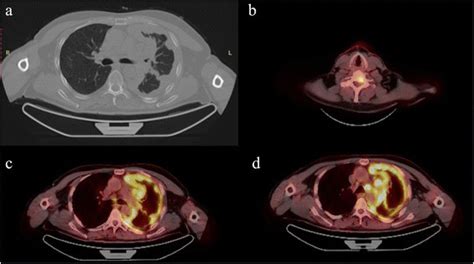

A PET scan, short for Positron Emission Tomography scan, is an advanced imaging test that helps doctors see how your tissues and organs are functioning at a cellular level. Unlike X-rays or CT scans that show anatomical structures, a PET scan reveals metabolic activity.

For mesothelioma, this means the scan can highlight areas where cells are more active, which can indicate the presence of cancer. Cancer cells often have a higher metabolic rate than healthy cells, making them "light up" on a PET scan after a special tracer is introduced into your body. This makes the Mesothelioma PET Scan a powerful tool for detection and evaluation.

Once your PET scan is complete, a radiologist will interpret the images and send a report to your doctor. They look for "hot spots" – areas where the tracer has accumulated more than usual – which can indicate cancerous activity.